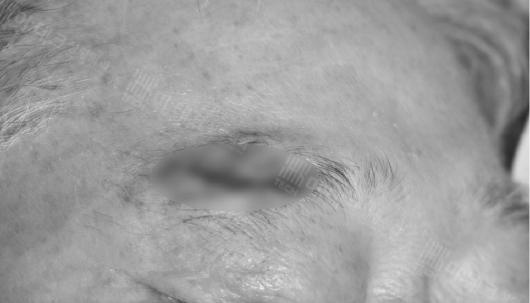

우측 눈썹 부위에 약 2.5cm 정도의 상처가 보입니다.

일반적으로 그냥 봉합을 해도 괜찮지만,

이렇게 무언가에 찍혀서 생긴 상처는 주변 조직을 정리하고 봉합을 해 주면 흉터가 훨씬 덜 남게 되죠.

이걸 변연절제술이라고 합니다.